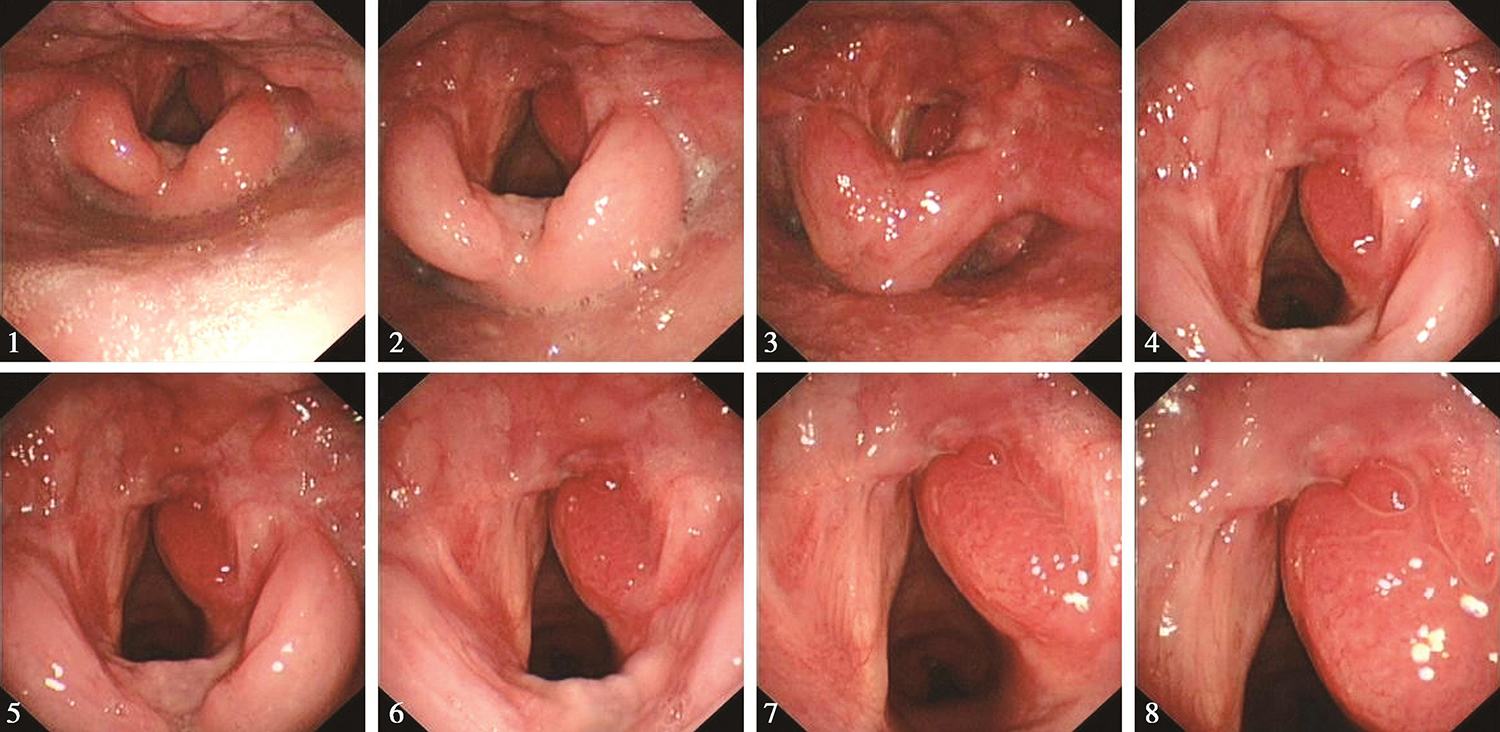

3.2017年3月15日电子内镜检查所见:“喉癌术后3个月”,鼻腔进镜顺利。鼻咽部结构完整,黏膜光滑,未见明显异常。口咽双侧扁桃体未见肿大。舌根部淋巴滤泡增生。下咽部表面基本平整,未见明显异常。喉部呈术后改变,会厌切除,双侧披裂保留,术区表面基本平整,左侧声带光滑,右侧声带肿胀明显,双侧声带活动正常(图3)。

图3 电子喉镜:术后3个月

内镜诊断:喉癌术后3个月,喉部呈术后改变,术区表面基本平整,右侧声带肿胀明显,肿瘤征象不明显,请继续随诊。

6.2017年11月1日门诊复查电子内镜检查见,喉癌术后10个月,喉部呈术后改变,术区表面基本平整,右侧声带略肿胀,肿瘤征象不明显(图4),请继续随诊。

图4 电子喉镜:术后10个月